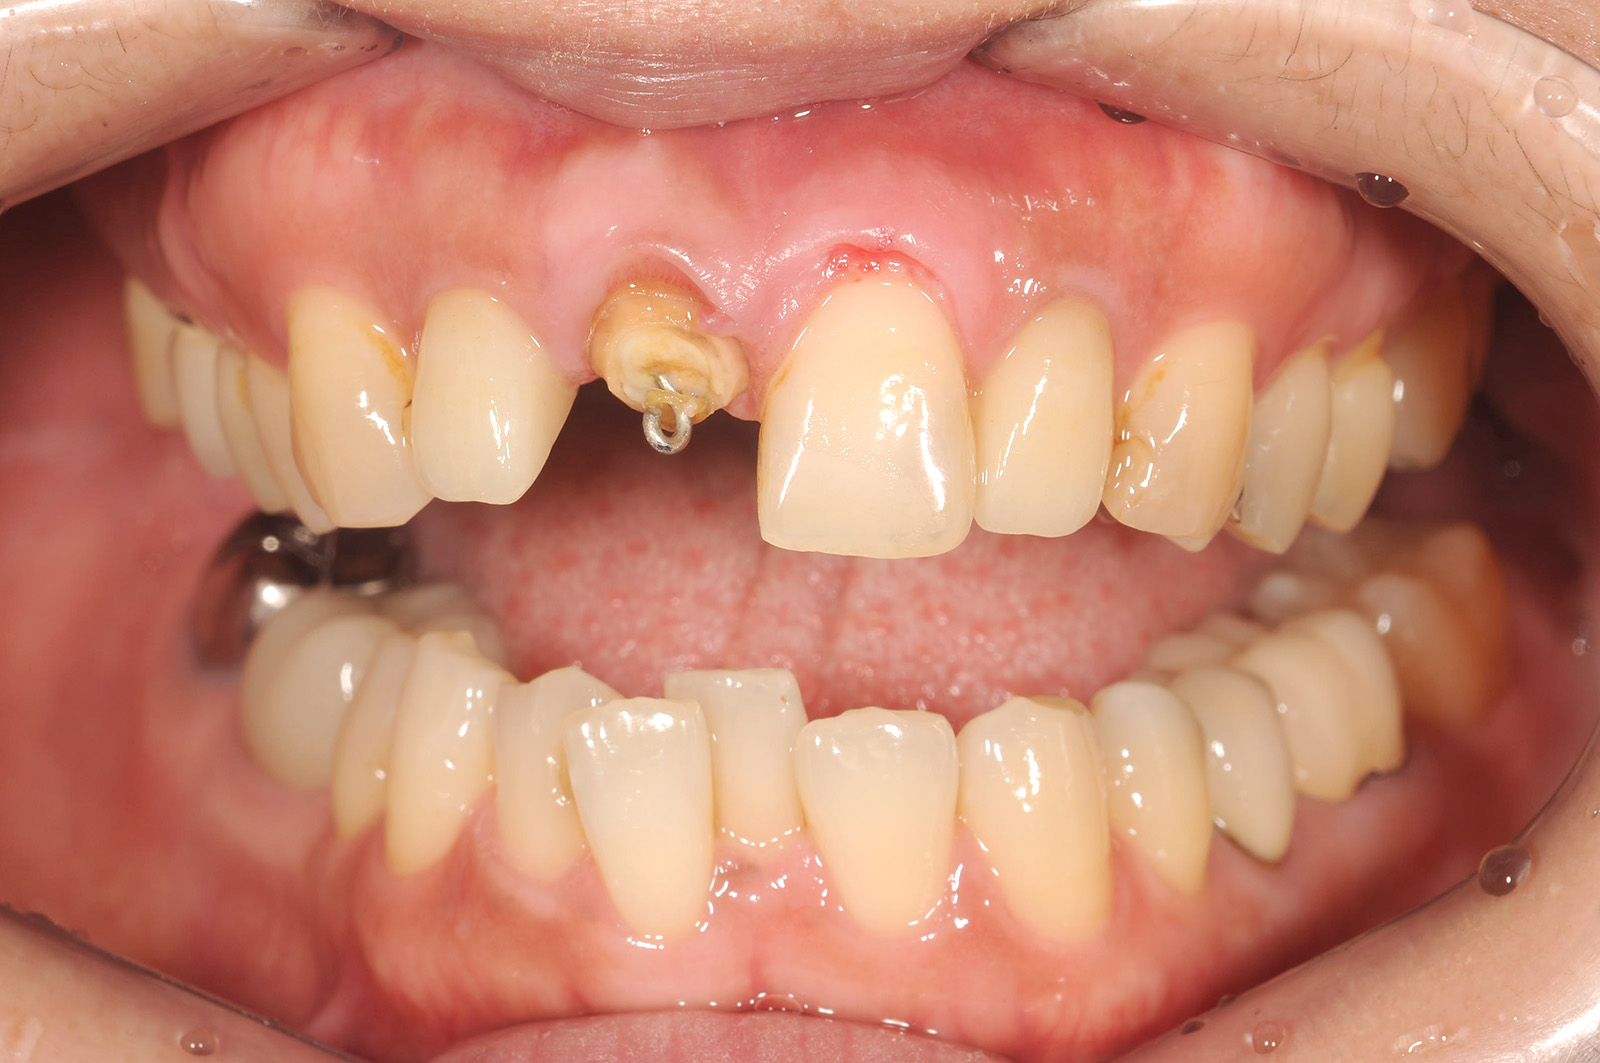

可能な限り「抜歯を避ける」治療

画像

右の写真のように、虫歯がひどく進行して歯が崩壊してしまうと、一般的には「抜歯」をすることになります。

抜歯した後は「インプラント」「入れ歯」「ブリッジ」の治療に進みますが、いずれの治療法も患者さんの負担が小さくありません。当院では、抜歯せずに治せる可能性がある症例については、抜歯を避ける治療法を提案します。

エクストリュージョン

一般的な虫歯の治療では、虫歯になった部分を削って被せ物を取り付けます。

虫歯がひどく進行して歯が崩壊してしまうと、被せ物を取り付ける場所がなくなってしまい、治療ができなくなってしまいます。一般的な歯科医院では抜歯と診断されますが、当院では、「エクストリュージョン」という治療法で、抜歯せずに治せることがあります。

「エクストリュージョン」は矯正治療の一種で、歯茎に埋もれた歯の根を外に引き出し、被せ物を取り付ける場所を作ります

• 治療前

• 治療後

主訴右上の前歯が折れた 他院では抜歯と言われた

どのように治療したのかの具体的な説明そのままではかぶせ物がかぶせられないのでエクストルージョン(矯正による挺出)を行った後に、歯ぐきのラインをそろえるためのクラウンレングスニング(歯茎を切って開いて、歯を支えている骨を整える処置)したのちにジルコニアクラウンにて修復

治療期間途中精密仮歯による経過観察期間もあるので約半年

治療費36.3万円

その治療をすることで起こり得るリスク歯根(歯の土台部分)が短くなることによる、動揺や破折のリスクがあがる